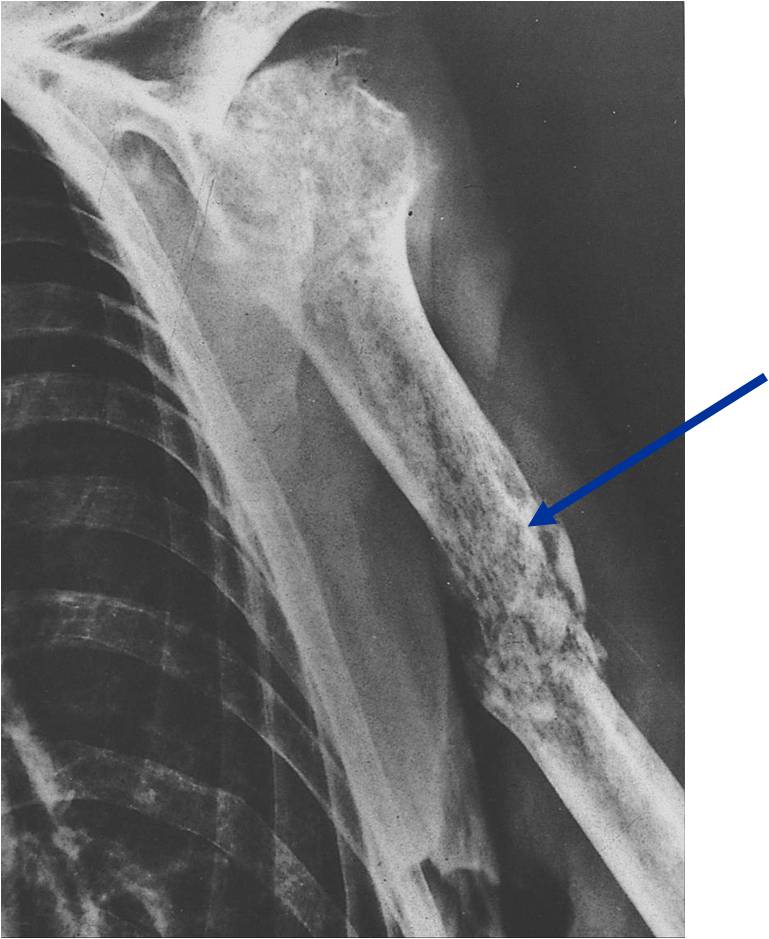

Permeative/Motheaten Lesion with Pathologic Fracture

- Permeative or moth eaten bone destruction (55%)

- Geographic (11%); Blow out (1%); Blastic (2%); Normal XR (5%)

- Metadiaphysis (75%)

- Periosteal reaction—may look benign

- Pathologic Fracture (22%)